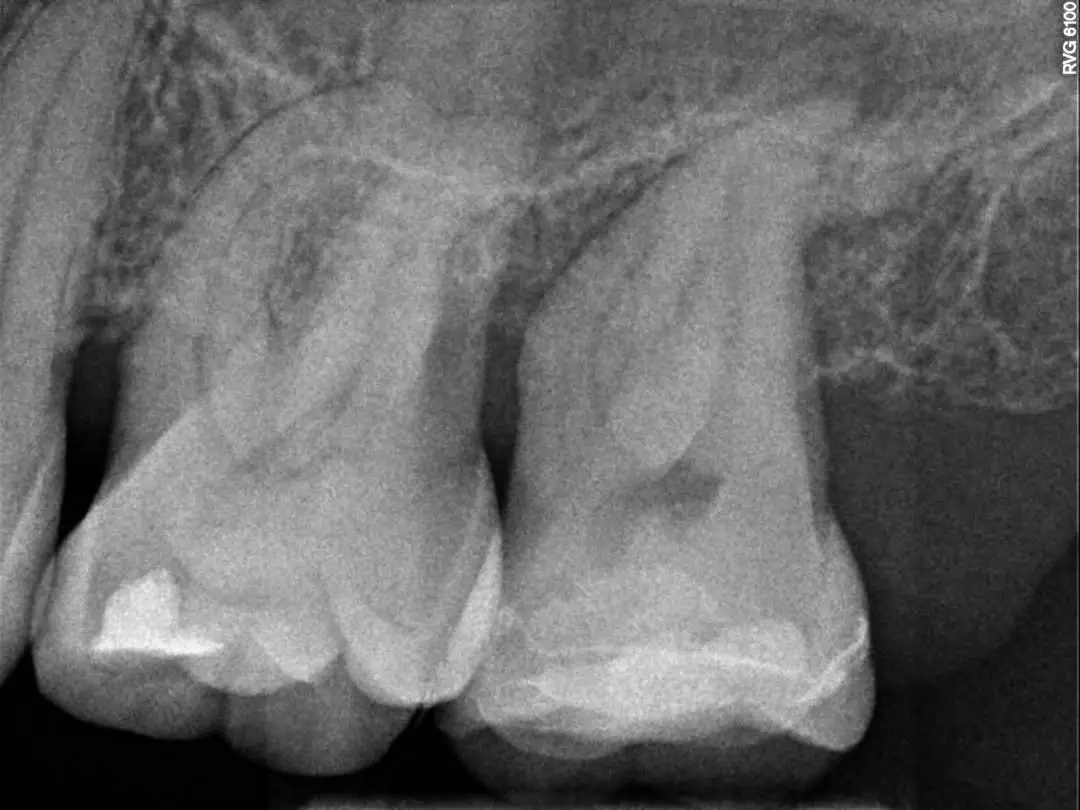

See the Difference Specialist Care Makes

Compare real treatment results through detailed before-and-after X-rays, showing how expert care restores dental health, precision, and long-term outcomes.